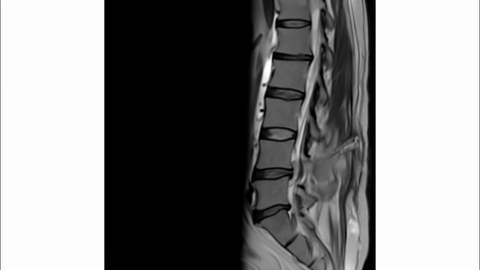

Reasoning Video Showcase

12Medical1.15 ± 1.171.56 ± 1.410.27 ± 0.390.30 ± 0.582.08 ± 1.561.81 ± 1.42